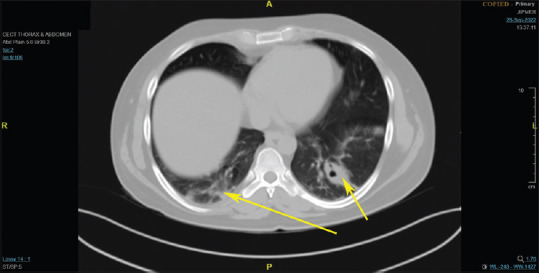

Melioidosis is a disease endemic to India but often goes unrecognized, leading to considerable illness and death. We present the case of a 31-year-old man who had a fever of unknown origin, abnormal renal and liver function tests, and negative tests for dengue, typhoid, leptospirosis, and scrub typhus. Imaging revealed multiple splenic infarcts. Initially suspected to be malaria due to its prevalence in South India, further investigation uncovered pneumonia along with several liver and splenic abscesses, raising the possibility of melioidosis. Blood culture eventually identified Burkholderia pseudomallei, confirming the diagnosis. As malaria cases decline in Southeast Asia, emergency physicians should consider melioidosis in their differential diagnosis of acute febrile illnesses, especially in endemic areas. Early detection and prompt antibiotic treatment are vital for managing this often under-recognized disease with a high fatality rate. Thus, melioidosis should be considered in patients with unexplained fever in endemic regions, as early diagnosis and intervention can be life-saving.